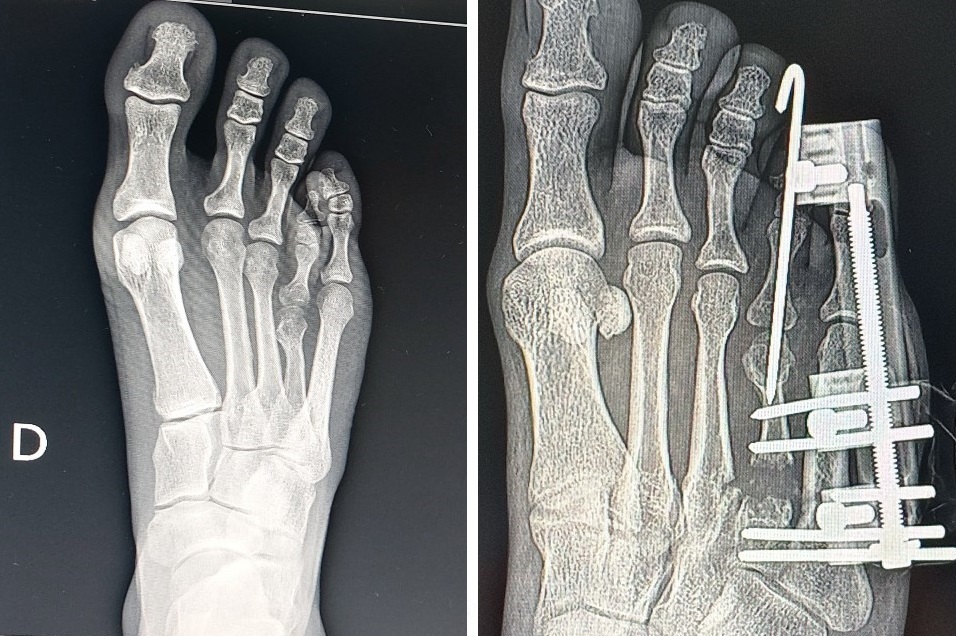

O Hospital Carlos Fernando Malzoni (HCFM) registrou um marco inédito em sua história recente ao realizar, no final de dezembro de 2025, uma cirurgia de braquimetatarsia, procedimento raro e de alta complexidade dentro da ortopedia especializada em pé e tornozelo, executado por meio de técnica percutânea, considerada menos invasiva em relação aos métodos tradicionais.

A braquimetatarsia é uma malformação congênita caracterizada pelo encurtamento anormal de um dos ossos do antepé, geralmente o quarto metatarso, condição que pode causar dor, alterações na marcha, dificuldade no uso de calçados e impacto estético significativo.

Segundo a paciente Letícia Siqueira, submetida à cirurgia no HCFM, a condição esteve presente desde a infância. “Desde muito cedo, convivi com o encurtamento do quarto metatarso do pé direito. Além da questão estética, que se intensificou na adolescência, eu sentia desconforto funcional constante. A maioria dos calçados me causava dor, atrito e até lesões”, relata.

O que torna o caso ainda mais singular é a forma como a cirurgia teve início, como explica o Dr. Lucas: “Durante uma aula para a turma dos alunos do 6º ano da Faculdade, a Letícia me mostrou o seu pé com um quadro de braquimetatarsia, e me perguntou se eu saberia tratar. Me relatou que já havia visitado diversos ortopedistas, sendo que nenhum tinha experiência prévia com tal tipo de cirurgia para correção do quadro. Respondi a ela que a Braquimetatarsia é extremamente rara, porém eu já havia realizada tal correção previamente, e que poderíamos resolver o seu caso. Imediatamente solicitei as radiografias no ambulatório do hospital e já iniciamos a nossa programação cirúrgica, com todo o apoio do HCFM”.

Letícia destaca que o processo ainda está em andamento, uma vez que o tratamento envolve o alongamento ósseo gradual, etapa que exige acompanhamento rigoroso. “Ainda estou na fase de alongamento ósseo, que é um processo lento e que exige paciência. Mas cada evolução representa uma melhora significativa, tanto do ponto de vista funcional quanto estético”, afirma.